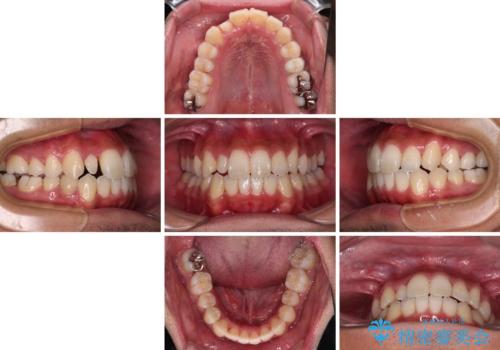

- 前歯のデコボコとクロスバイトを気にして来院された患者様です。

下顎の歯列弓に対して上顎歯列弓がやや小さく、側方の歯を中心にクロスバイトが見受けられました。

後方に隠れていた上顎前歯は矮小歯であるため、矯正治療の途中でオールセラミッククラウンを装着し、左右対称の大きさでの仕上がりを目指すこととしました。

奥歯の咬み合わせは接触が少なく物足りないように見えますが、患者様としては十分に咬むことができるとのことでした。